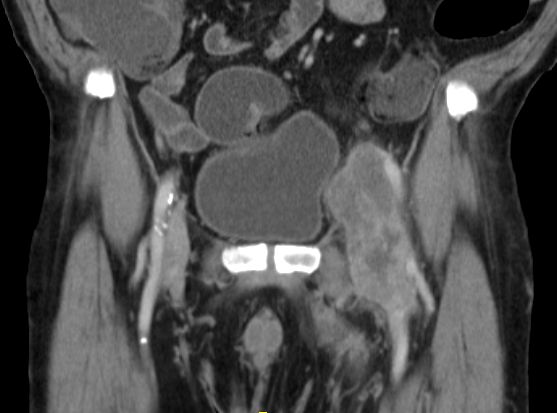

| Leiste | 72-jähriger Landwirt mit einem Leiomyosarkom der linken Leiste pT2b pN0 G2 R0. 110 x 50 x 50 mm großer, solider Tumor mit enger Lagebeziehung zum Gefäßbündel.

Infiltration des Musculus rektus abdominis.![]() |

![]() |

![]() | ||